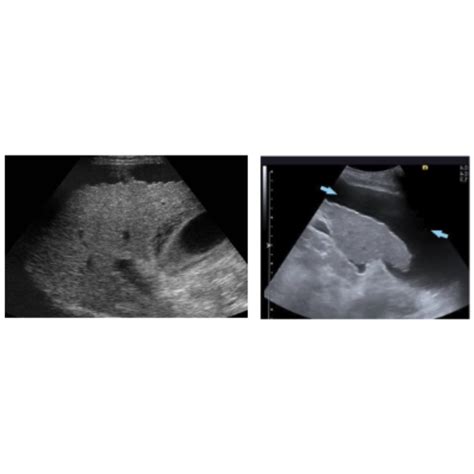

Interpreting the results of a Parenquima Hepatico Izquierdo Ecografia involves analyzing the ultrasound images for any abnormalities in the left hepatic parenchyma. Common findings include:

• Hepatic Lesions: These can be benign or malignant and may appear as cysts, tumors, or nodules.

• Fatty Liver Disease: Characterized by the accumulation of fat in the liver, which can appear as a bright, echogenic pattern on ultrasound.

• Liver Cirrhosis: Advanced liver disease that can show signs of fibrosis, nodularity, and altered liver texture.